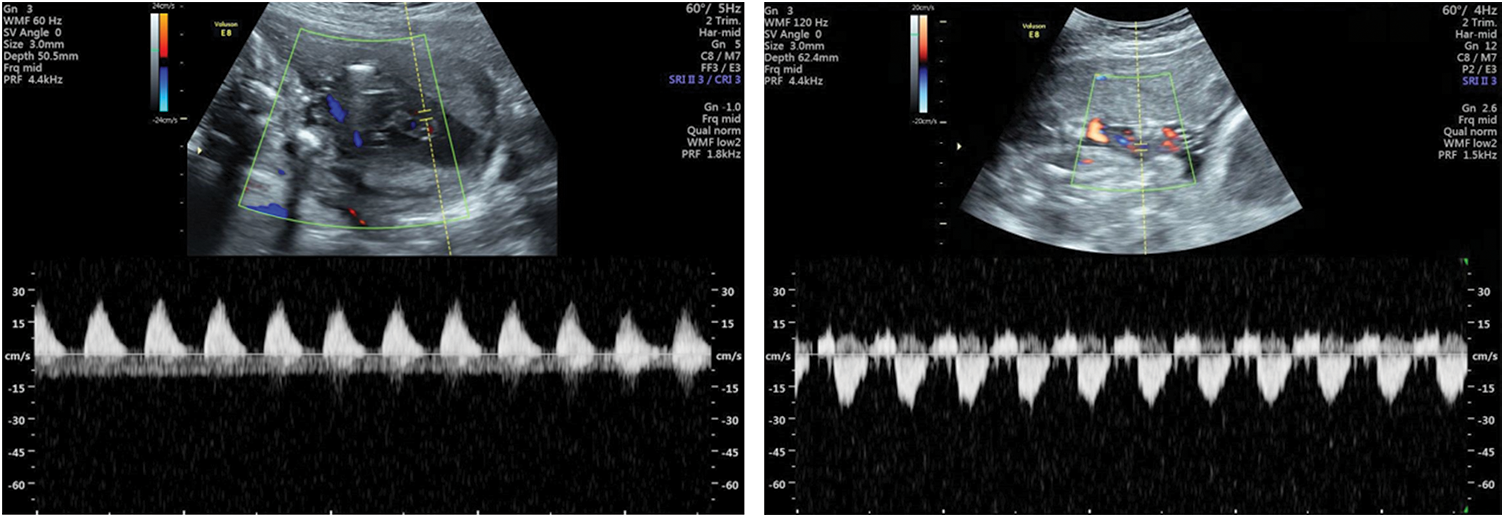

In some abnormal conditions, the placental blood flow resistance increased, and the umbilical artery blood flow resistance increased accordingly. Ultrasound showed this situation that the end-diastolic blood flow disappeared or reversed (Fig. 4), and PI, RI, and S/D increased. The disappearance or reversal of end-diastolic blood flow is a characteristic change of severe deficiency of fetal-placental circulation, suggesting that the fetus is severely hypoxic or close to the decompensated stage of hypoxia. It is mainly found in intrauterine growth restriction and placental dysfunction. Combined with the maternal and fetal conditions, the appropriate delivery time can be chosen for the fetus according to the result of Doppler examination.

Figure 4: Umbilical arteries visualized by transabdominal color flow mapping and Doppler velocity waveforms: Loss of diastolic blood flow at 22 weeks (left); reversal of diastolic blood flow at 25 weeks (right)